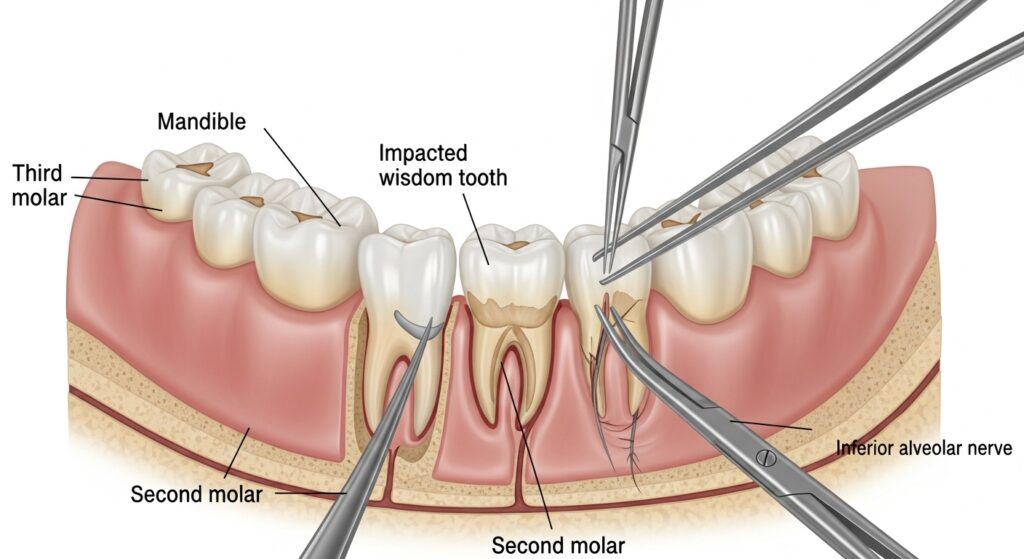

Once you are anesthetized and comfortable, your oral surgeon in Lakeland will begin the procedure. For surgical tooth removal, the surgeon may need to create a small cut in your gum. They may also need to remove a small amount of bone to get the tooth. If the tooth is impacted, the surgeon may need to break it down into smaller pieces to remove it easily. After removal, your dentist will clean and stitch the wound if it requires.

- Nerve injury: In some cases, nerves near the wisdom teeth may be damaged. This might result in numbness or tingling in the tongue, lips, and chin. Usually, this feeling is very temporary.